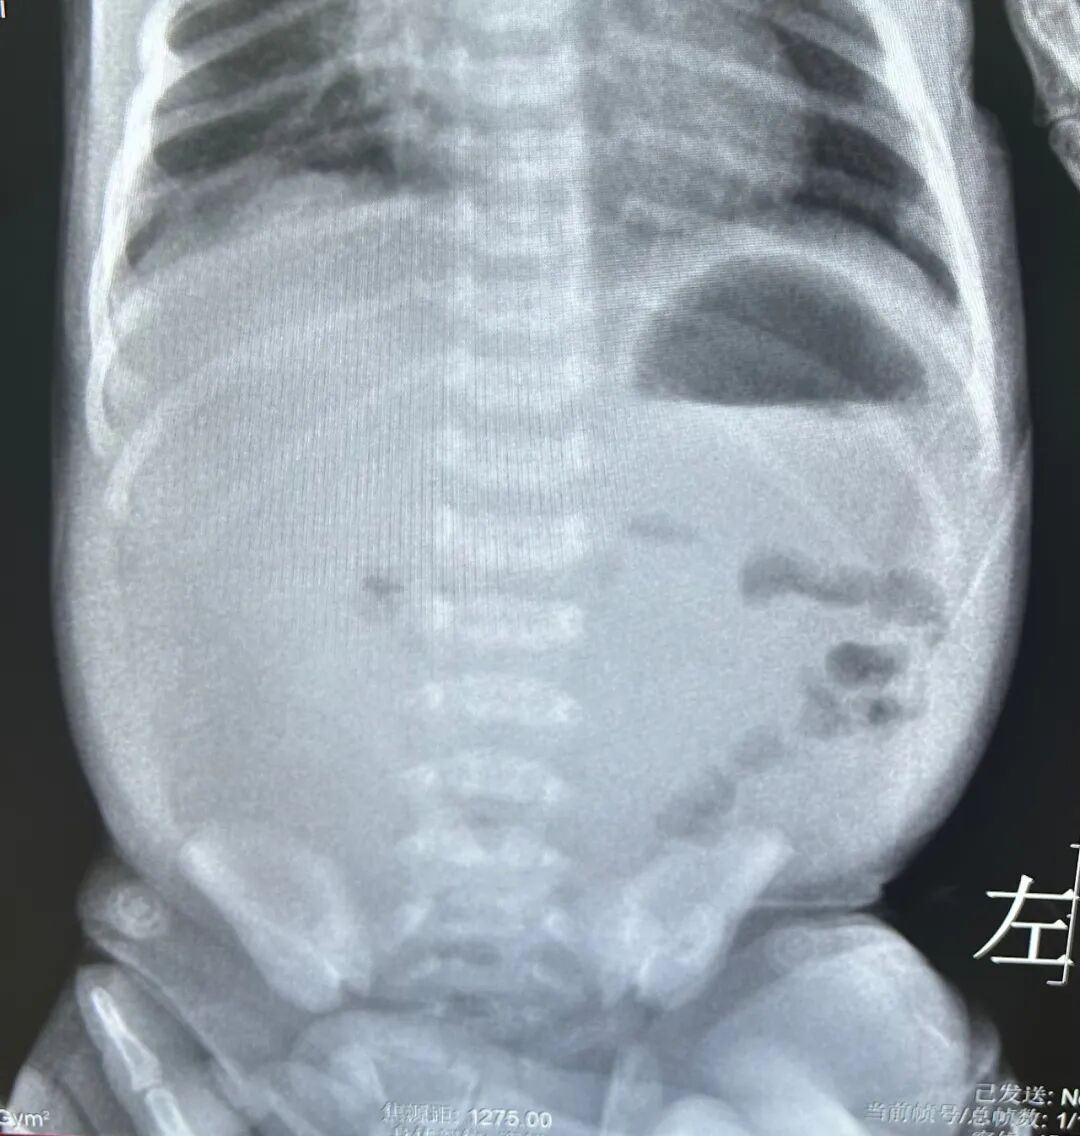

张伟主治医师与吴琼主管护师火速准备转运设备,1小时内便将贝贝安全转入科室。入院后,医护团队快速完成生命体征监测、电解质及血气分析等检查,张伟陪同患儿完成超声检查,最终确诊为先天性肠旋转不良合并肠扭转540度,手术刻不容缓。

医护团队一边安抚濒临崩溃的患儿家长,高效完成术前谈话与准备工作;一边由张艳霞与张伟联手,为贝贝实施腹腔镜肠扭转复位+Ladd's术。术中可见患儿腹腔已出现乳糜性腹水,肠系膜、肠壁附着乳糜液体,淋巴管回流异常,肠管随时面临缺血坏死的危险。